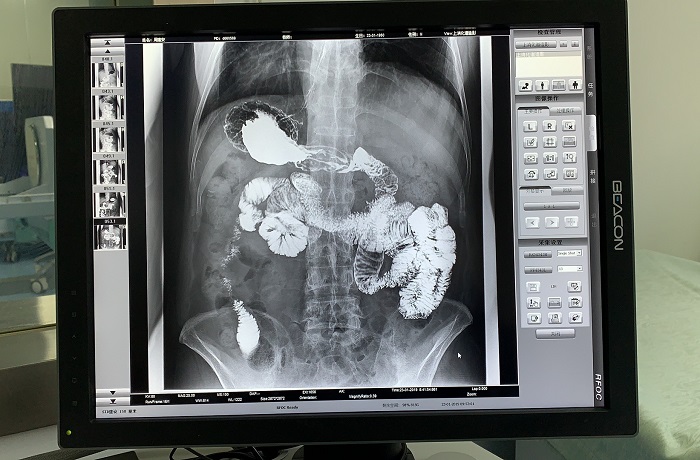

同時(shí),在透視過程中可實(shí)時(shí)點(diǎn)片,實(shí)現(xiàn)快速動(dòng)靜態(tài)圖像切換,尤其是在食道造影中優(yōu)勢明顯,可快速捕捉病變部位影像,還具有視頻保存回放功能,病人檢查結(jié)束后,仍可通過視頻回放對病人進(jìn)行診斷,不需要重復(fù)檢查。

除鋇劑灌腸之外,動(dòng)態(tài)DRF還適用于胃腸道造影檢查,子宮輸卵管造影等。同時(shí),動(dòng)態(tài)DRF作為普通數(shù)字X光機(jī)使用,滿足全身各部位的數(shù)字化攝影檢查需求;作為具有透視功能的胃腸機(jī)使用,滿足全身各部位的數(shù)字化透視、透視下定位、透視下穿刺、透視下點(diǎn)片及簡單的介入治療需求,全面適用于醫(yī)院體檢科、內(nèi)科、外科、骨科、創(chuàng)傷科、急診科等多個(gè)科室臨床診斷。

胃腸道造影高清影像